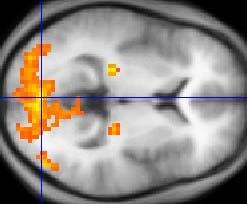

The Ready View advanced visualization platform provides a combination of protocols, applications and advanced tools that enable a fast, easy and quantified analysis. In addition to standard and advanced protocols, such as 4-D review and image averaging, Ready View offers fast and accurate multiparametric protocols, such as brain oncology, knee, liver and many more. Multiparametric protocols offer a new, simple and intuitive workflow to process all functional data from a single screen without having to leave a reading station.

Combining Ready View’s robust accessibility with its many productivity tools such as auto-processing, save state, one-click motion correction, and real time thresholding and segmentation, Ready View will not only help streamline image processing and analysis but will also help clinicians provide an effective diagnosis.